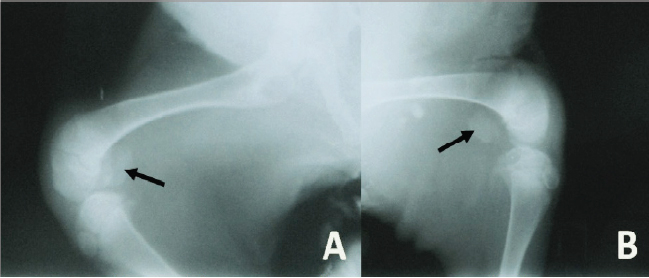

Radiographically, the stifle areas of the affected goats showed ventrocaudal PL in three cases (Figs. 2 and 3) and dorsal PL in the other two cases, for which surgical treatment was performed (Fig. 4A).

Fig. 4. (A) Mediolateral radiograph of the right stifle of a 10-month-old goat showing a dorsal PL (arrow) with no signs of trochlear ridge hypoplasia. There is also an avulsion fracture of the tibial tuberosity (star). (B) Mediolateral radiograph of the right stifle of the same goat immediately postsurgery showing that the patella (arrow) and the tibial tuberosity (star) are placed almost at their normal anatomical locations.